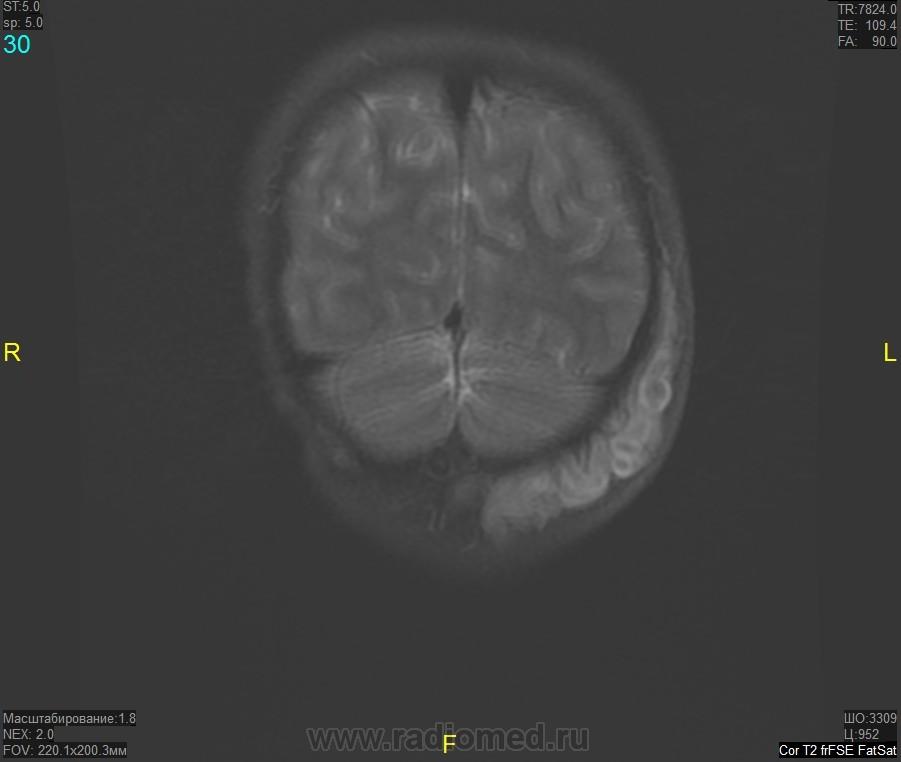

Уважаемые коллеги! Прошу консультативной помощи. Про пациента известно: девочка (7 лет), в анамнезе 2,5 года назад травма головы. Не диагностировалась. Периодически жалобы на болезненность при пальпации затылочной области(((((

как будто связь с ликвором имеется.  Дополнил бы венографией, и FatSat"ом ну и контрастом, конечно.

Нейрофиброма вполне может быть. Плексиформная. Проверить на нейрофиброматоз. Я видел такой же структуры и локализации. Пятен на коже нет? Вообще на теле? И нет ли чего похожего в позадиглоточном пространстве?

есть похожее образование в позадиглоточном пространстве)

многоузловое образование  исходящее из задней части предпозвоночного пространства с переходом на подкожную жировую клетчатку головы!шваннома ,нейрофиброма и их злокачественные аналоги